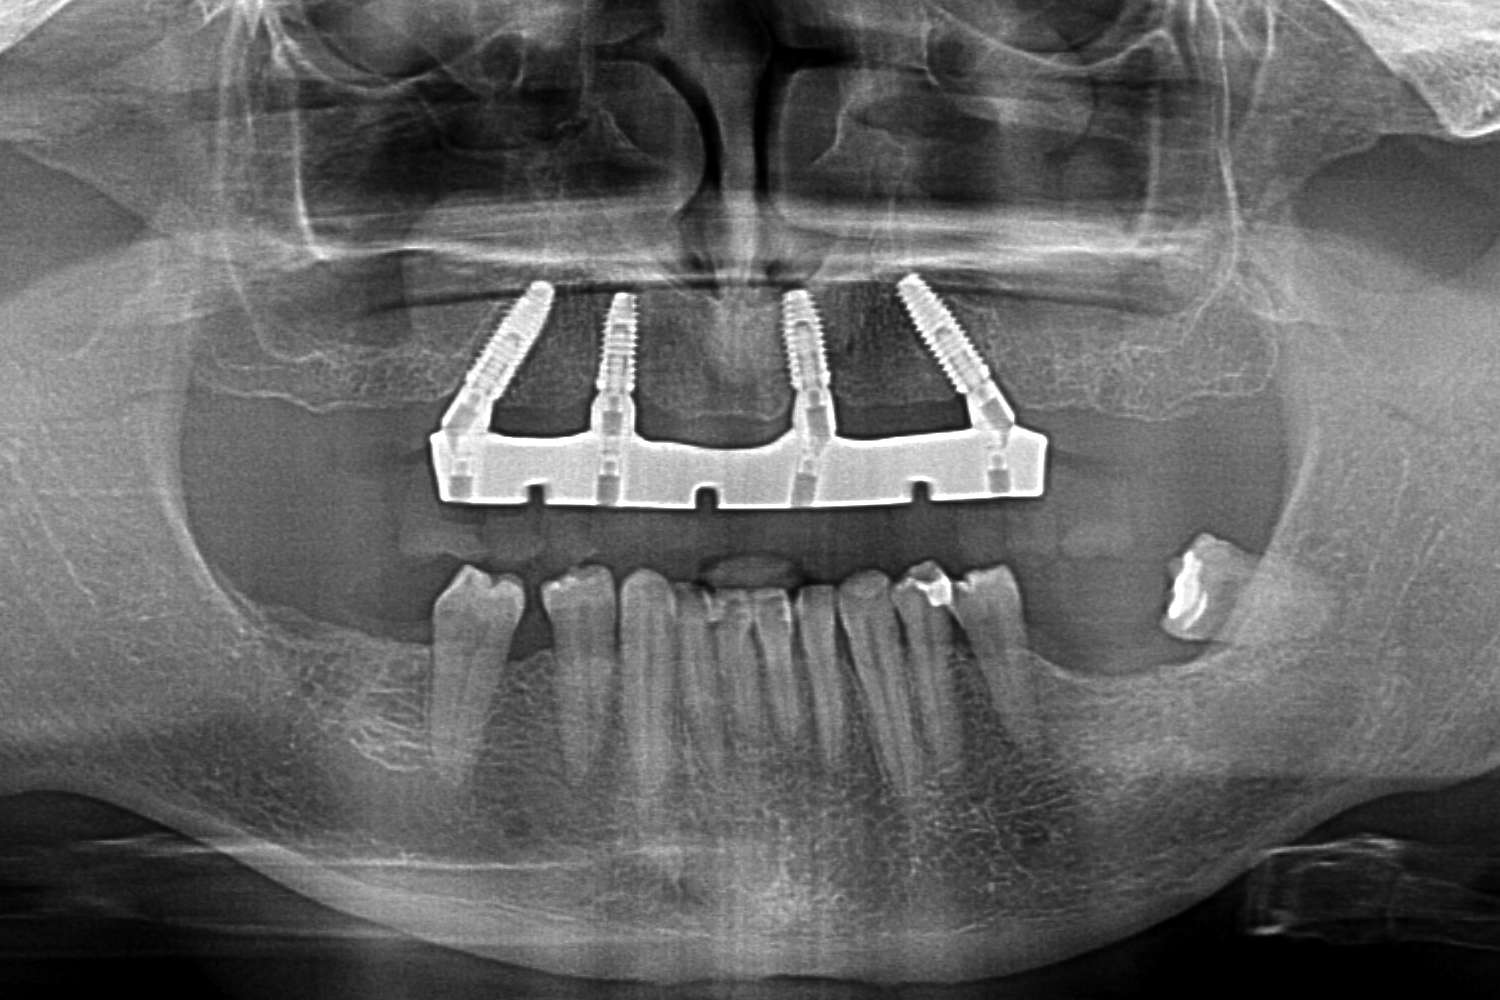

1. Proteza wykonana wg protokołu All On X

Metoda All On X to rewolucyjne podejście do odbudowy całej szczęki na implantach. Polega na osadzeniu pełnej protezy stałej na odpowiedniej liczbie implantów (zwykle 4-6), strategicznie rozmieszczonych w kości szczęki lub żuchwy. Liczba implantów jest dobierana indywidualnie do każdego pacjenta – stąd nazwa “All On X”, gdzie X oznacza optymalną dla danego przypadku liczbę wszczepów.

– Pełna odbudowa uzębienia na 4-6 implantach

Proteza wykonana w technice All On X może przez długi okres funkcjonować jako uzupełnienie samodzielne i jest najczęściej wstępem do wykonania stałych uzupełnień protetycznych np. mostów porcelanowych przykręcanych dna implantów

Przypadek 1